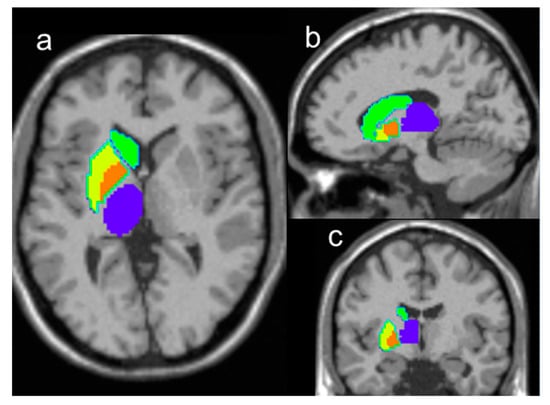

4.2. MR Examination and Data Processing